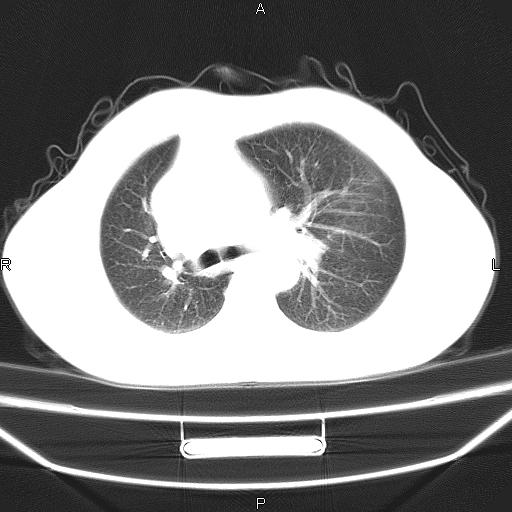

患者,男。50岁。近几日有咳嗽症状,无其他不适,既往病史无,考虑膈疝。请前辈们看看指导指导。

膈膨升,左下肺通气不良,膈肌好像还完整。

考虑左侧膈疝。

左侧膈疝。

符合隔膨升,膈肌较完整。